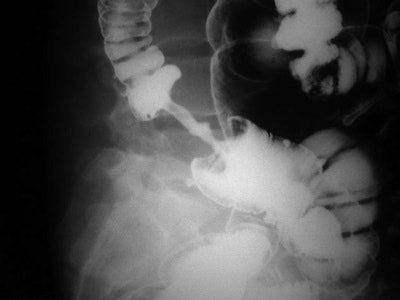

Apple core lesion: The annular carcinoma of the colon produces focal circumferential thickening of the bowel wall and narrowing of the colonic lumen, associated with shouldering. On a barium exam, the affected colon looks like a partially eaten apple.